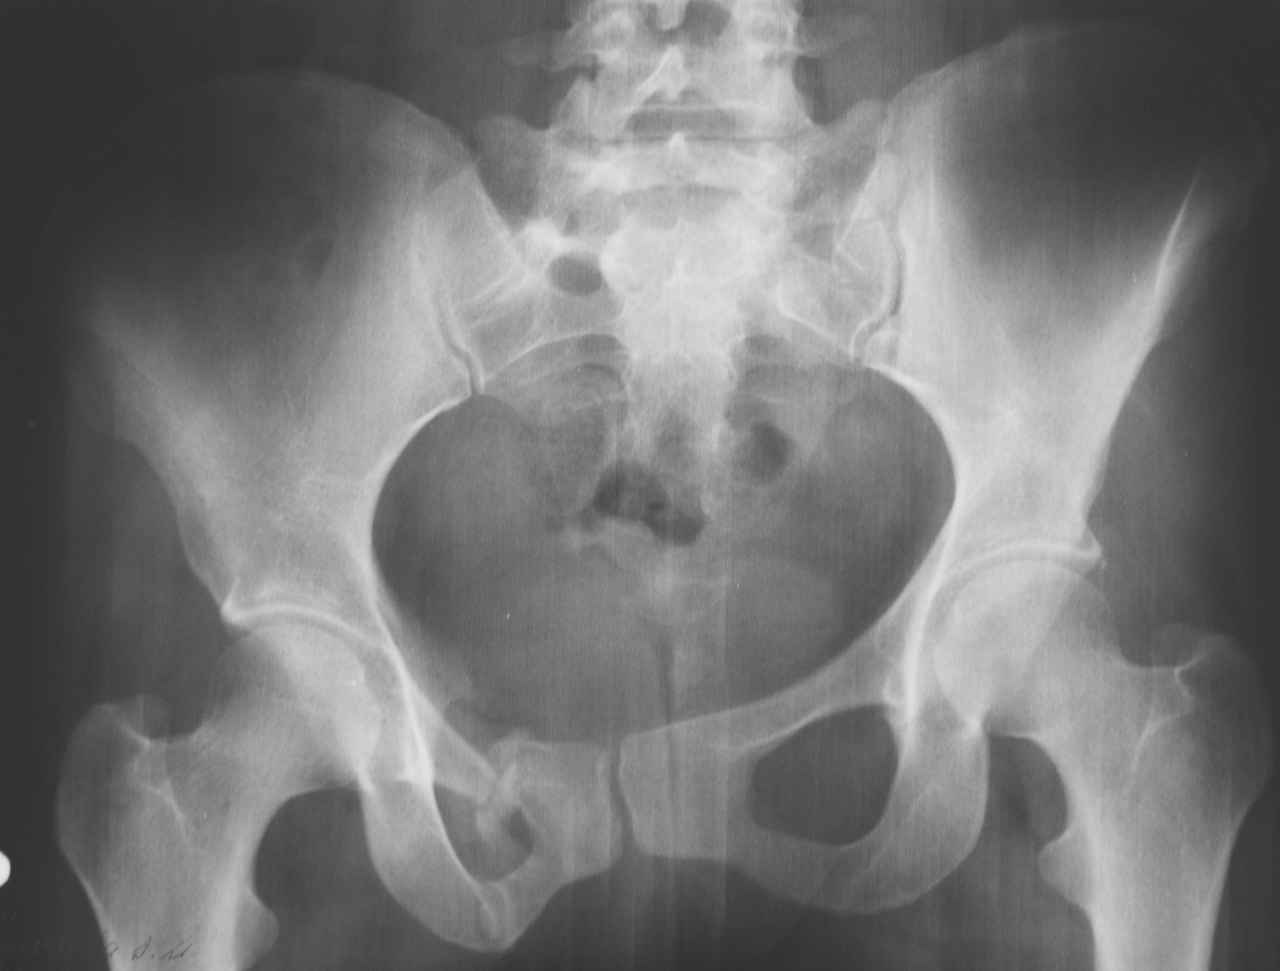

К нам в клинику поступила пациентка 30 лет с диагнозом: Постравматическая ротационная стабильная деформация тазового кольца.

Относительное укорочение левой н\конечности на 1 см. Левосторонний компенсаторный сколиоз 2 ст. Болевой синдром.

травма автодорожная в январе 2003г. Пассажирка переднего сидения ваз 2109. лечились положением по Волковичу.

С марта 2003 года жалуется на боли в тазу, ппояснице усиливающиеся при движении. В настоящее время жалобы на боли в области крестца, КПС больше слева, в пояснично-крестцовом отделе позвоночника. неприятные ощущения, щелчок при выпрямлении правого тазобедренного сустава из положения полного сгибания. боли в тазу появляются при ходьбе ч\з 100 м, так же при вставании из положения сидя, после сидения в течении 2-3 часов. при ходьбе более 100 м появпяется зябкость стоп больше справа. ходит при помощи трости в правой или в левой руке. без трости боли появляются сразу после начала ходьбы.

пальпация болезненна в паравертебральных точках средне-грудного и пояснично-крестцового отделов позвоночника, КПС с обеих сторон.

Объем движений в тазобедренных суставах полный. правый КПС заблокирован.

симптомы натяжения с обеих сторон отрицательны. С 2003г. лечится консервативно, получала ЛФК, массаж, физиолечение - без эффекта. в 2005г. лечилась в санатории с ортопедическим уклоном, получала плавание в минеральной воде, магнитотерапия, массаж, ЛФК. отмечала умеренное улучшение в течении 2 недель. Вопросы: надо ли оперировать, т.е. устранять относительное укорочение левой н\конечности и как?Если не оперировать, то как лечить консервативно? Р-граммы, КТ прилогаются.